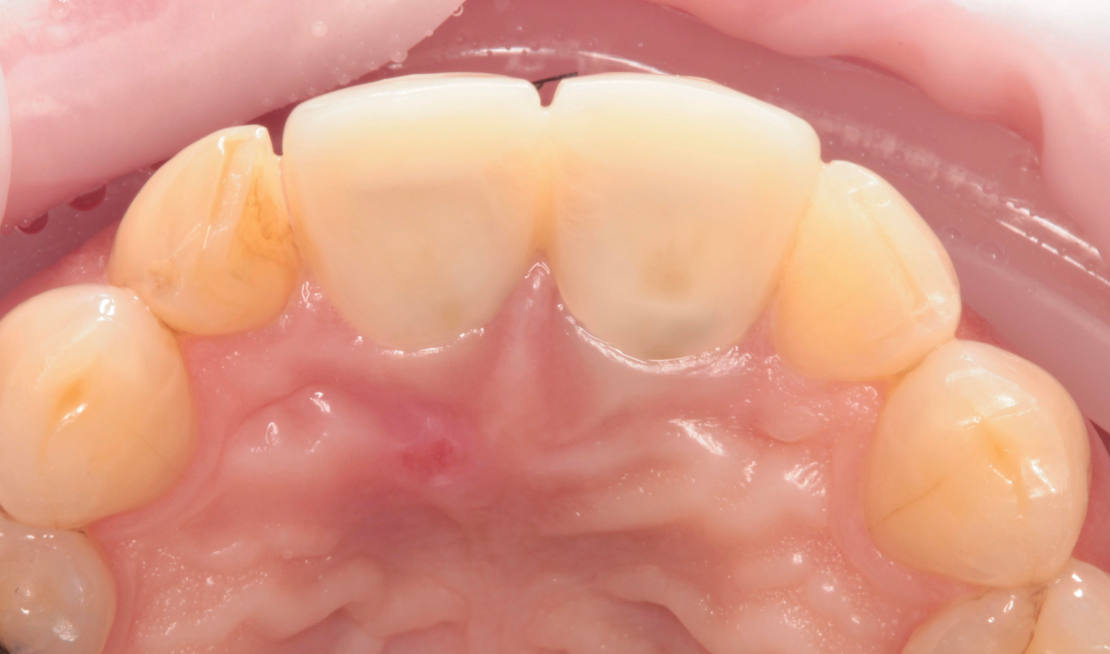

45-ročná pacientka sa obrátila na našu kliniku s bolesťou v oblasti horných stredných rezákov (obr. 1). Pri dôkladnom vyšetrení a CT diagnostike bola v oblasti zuba č. 11 zistená vertikálna fraktúra koreňa (obr. 2). V oblasti zuba č. 21 palatinálne bol prítomný hlboký kaz koreňa (obr. 3).

Vďaka týmto postupom bola operácia veľmi rýchla a pacientka odišla z ordinácie plne rehabilitovaná. Minimálne invazívnym spôsobom boli extrahované horné jednotky (obr. 6).